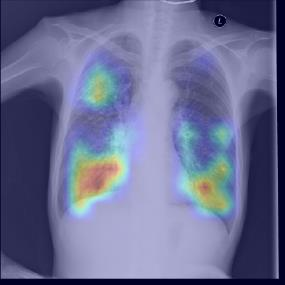

Chest X-ray (CXR) is the most typical diagnostic X-ray examination for screening various thoracic diseases. Automatically localizing lesions from CXR is promising for alleviating radiologists' reading burden. However, CXR datasets are often with massive image-level annotations and scarce lesion-level annotations, and more often, without annotations. Thus far, unifying different supervision granularities to develop thoracic disease detection algorithms has not been comprehensively addressed. In this paper, we present OXnet, the first deep omni-supervised thoracic disease detection network to our best knowledge that uses as much available supervision as possible for CXR diagnosis. We first introduce supervised learning via a one-stage detection model. Then, we inject a global classification head to the detection model and propose dual attention alignment to guide the global gradient to the local detection branch, which enables learning lesion detection from image-level annotations. We also impose intra-class compactness and inter-class separability with global prototype alignment to further enhance the global information learning. Moreover, we leverage a soft focal loss to distill the soft pseudo-labels of unlabeled data generated by a teacher model. Extensive experiments on a large-scale chest X-ray dataset show the proposed OXnet outperforms competitive methods with significant margins. Further, we investigate omni-supervision under various annotation granularities and corroborate OXnet is a promising choice to mitigate the plight of annotation shortage for medical image diagnosis.